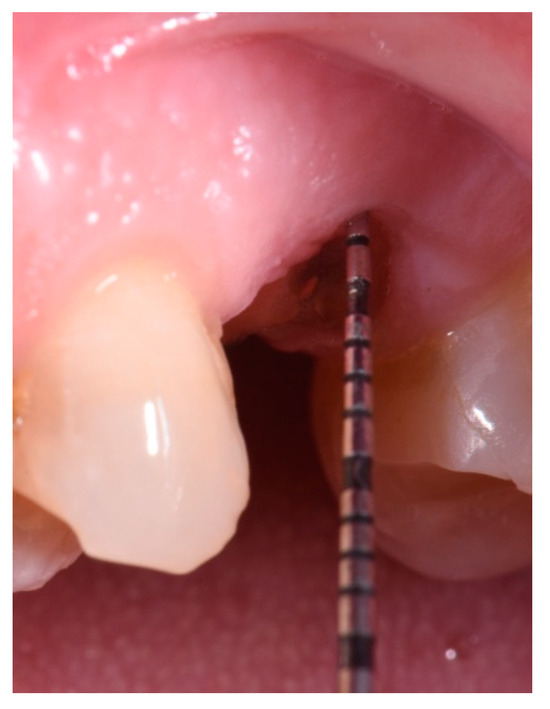

- Measurement in mm of the depth of insertion of the instrument into the gingival sulcus;